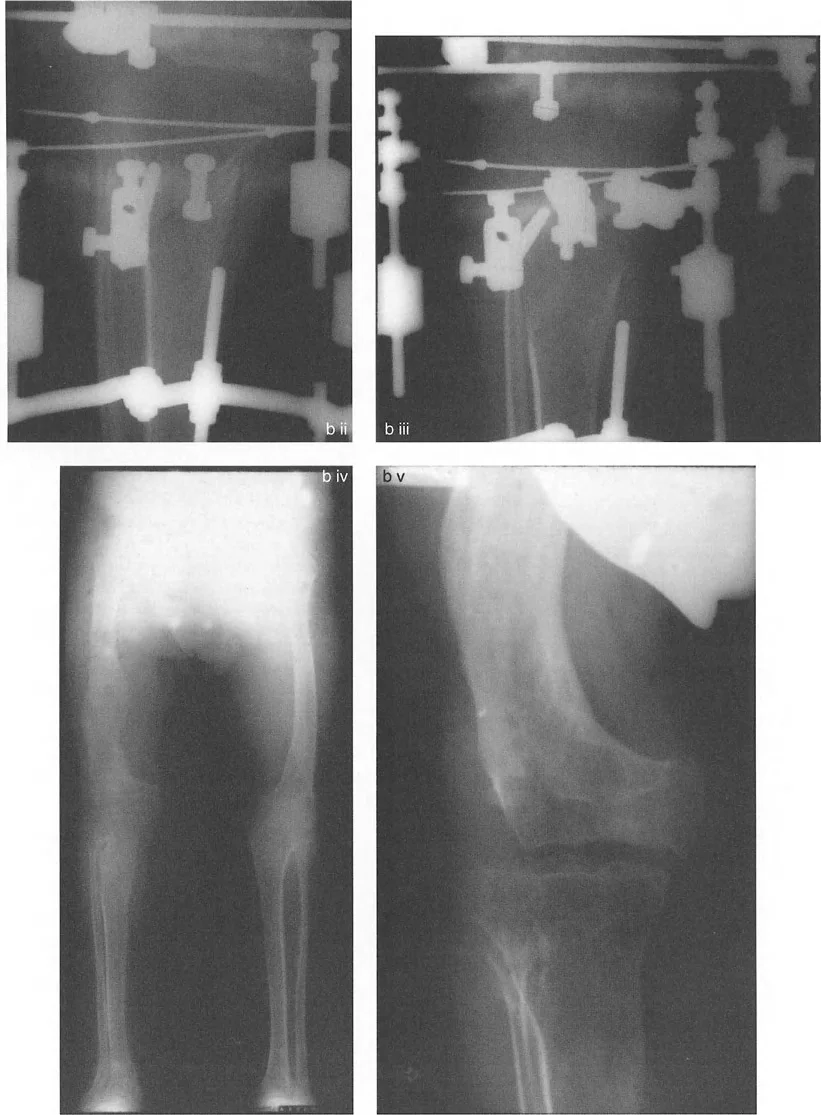

التصوير الإشعاعي المتقدم: مفتاح فهم التشوه

لا يمكن الحكم على المحاذاة والاتجاه بدقة إلا باستخدام صور الأشعة السينية الطويلة للطرف السفلي بالكامل في وضع الوقوف (فيلم بطول 51 بوصة). الأفلام التي تُؤخذ والمريض مستلقٍ أو أفلام الركبة القصيرة غير كافية تمامًا لتخطيط تصحيح التشوه.

نصائح مهمة للأشعة السينية الدقيقة:

- توجيه الرضفة: الدوران الصحيح للطرف أثناء الأشعة السينية أمر بالغ الأهمية. تكون الأشعة السينية صالحة فقط إذا كانت الرضفة متمركزة تمامًا بين لقمات الفخذ وموجهة للأمام مباشرة.

- وضع القدم غير ذي صلة: لا تضع المريض بناءً على زاوية تقدم القدم. إذا كان المريض يعاني من التواء في الساق للخارج، فإن وضع القدم للأمام سيؤدي إلى دوران داخلي للركبة، مما يبطل تمامًا قياسات مستوى التاج. دائمًا ما تُؤخذ الأشعة السينية بناءً على الركبة (الرضفة للأمام).

- ارتفاع الشعاع: يجب أن يتمركز شعاع الأشعة السينية عند مستوى مفصل الركبة من مسافة قياسية (عادة 10 أقدام) لتقليل أخطاء التكبير والتزيح.